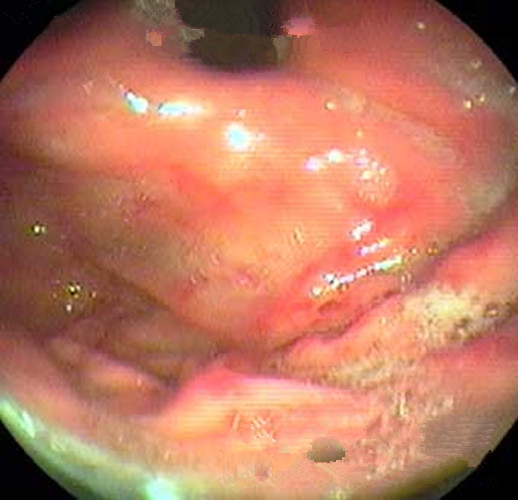

萎縮淺表性慢性胃炎

萎縮性的慢性胃炎

萎縮性慢性胃炎